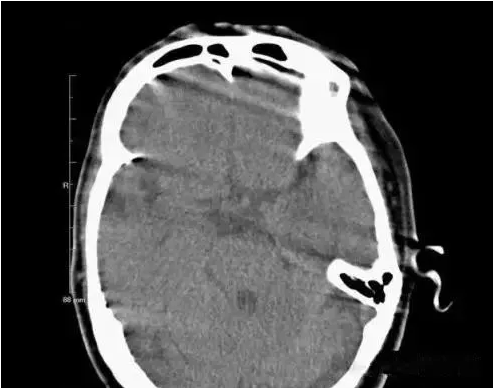

2.異物偽影:主要為密度差別極大的物體如金屬和人體組織一起掃描時所造成,偽影的特點是沿著高密度物體呈放射狀排列。有時圖像上不一定能直接看到目標異物,但只要仔細觀察偽影的放射狀搏列方向,即能找到異物的來源。